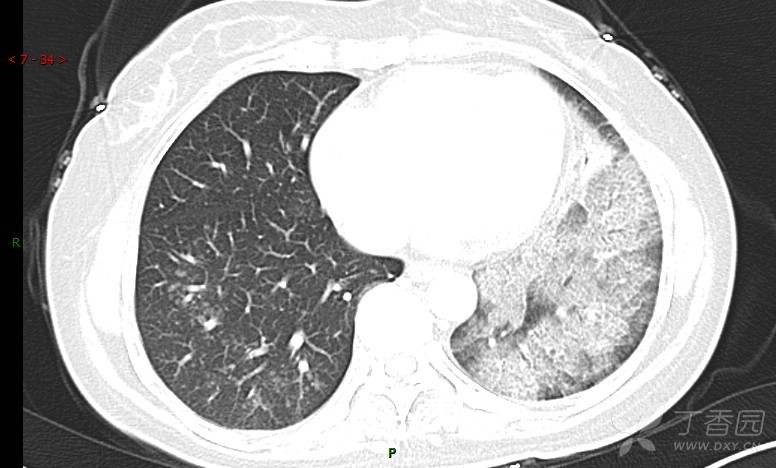

腺泡结节影,蜂窝征,这些都在提示……(病例3连发,附其他2例链接,病理已公布)

咳嗽1年余,加重7天。

患者于1年余前始受凉后出现咳嗽,多为干咳,未在意,未到医院就诊。近3月患者出现咳痰,多为黄色粘痰,量大,伴乏力,偶有头晕、心慌,无发热、胸痛、憋喘,无低热、盗汗、咯血、胸痛,无头痛,无恶心、呕吐、腹痛、腹泻,无尿频、尿急、尿痛,在当地诊所给予抗感染等对症支持治疗(具体药物及剂量不详),症状仍时有反复。患者于1月余前到外院就诊,行胸部CT提示双肺炎症,左肺重,考虑为“间质性肺炎”,给予“左氧氟沙星、利巴韦林、头孢哌酮舒巴坦钠注射液”治疗,复查胸部CT示病灶吸收不理想,后出院继续于诊所对症治疗(具体药物及剂量不详),效果欠佳。7天前患者无明显诱因出现上述症状加重,为求进一步诊治,特来我院就诊,我院门诊以“肺炎(重症)?”收入留观室,留观室给予“盐酸莫西沙星氯化钠”等对症治疗后,今日转入我科。患者自发病以来,神志清,精神差,饮食正常,睡眠增多,大小便正常,体重近3月减轻5公斤余。